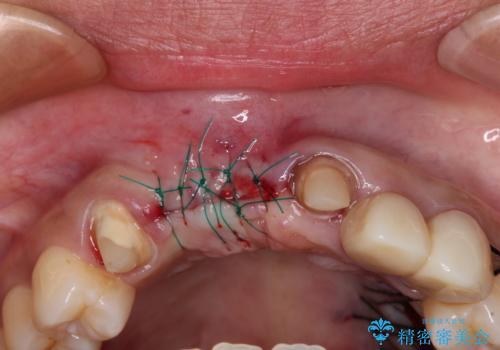

歯肉が痩せてしまっている状態を改善するため、口蓋から歯肉の結合組織を採取し、移植することで厚みを増大させることとし、その後オールセラミックブリッジにて補綴治療を行うこととしました。

1回の歯肉移植により歯肉の厚みは大幅に改善されましたが、折角なのでもう少し大きくしたいとの要望があり、2回目の処置も行うこととしました。

厚みも高さも十分な歯肉量を獲得することができました。